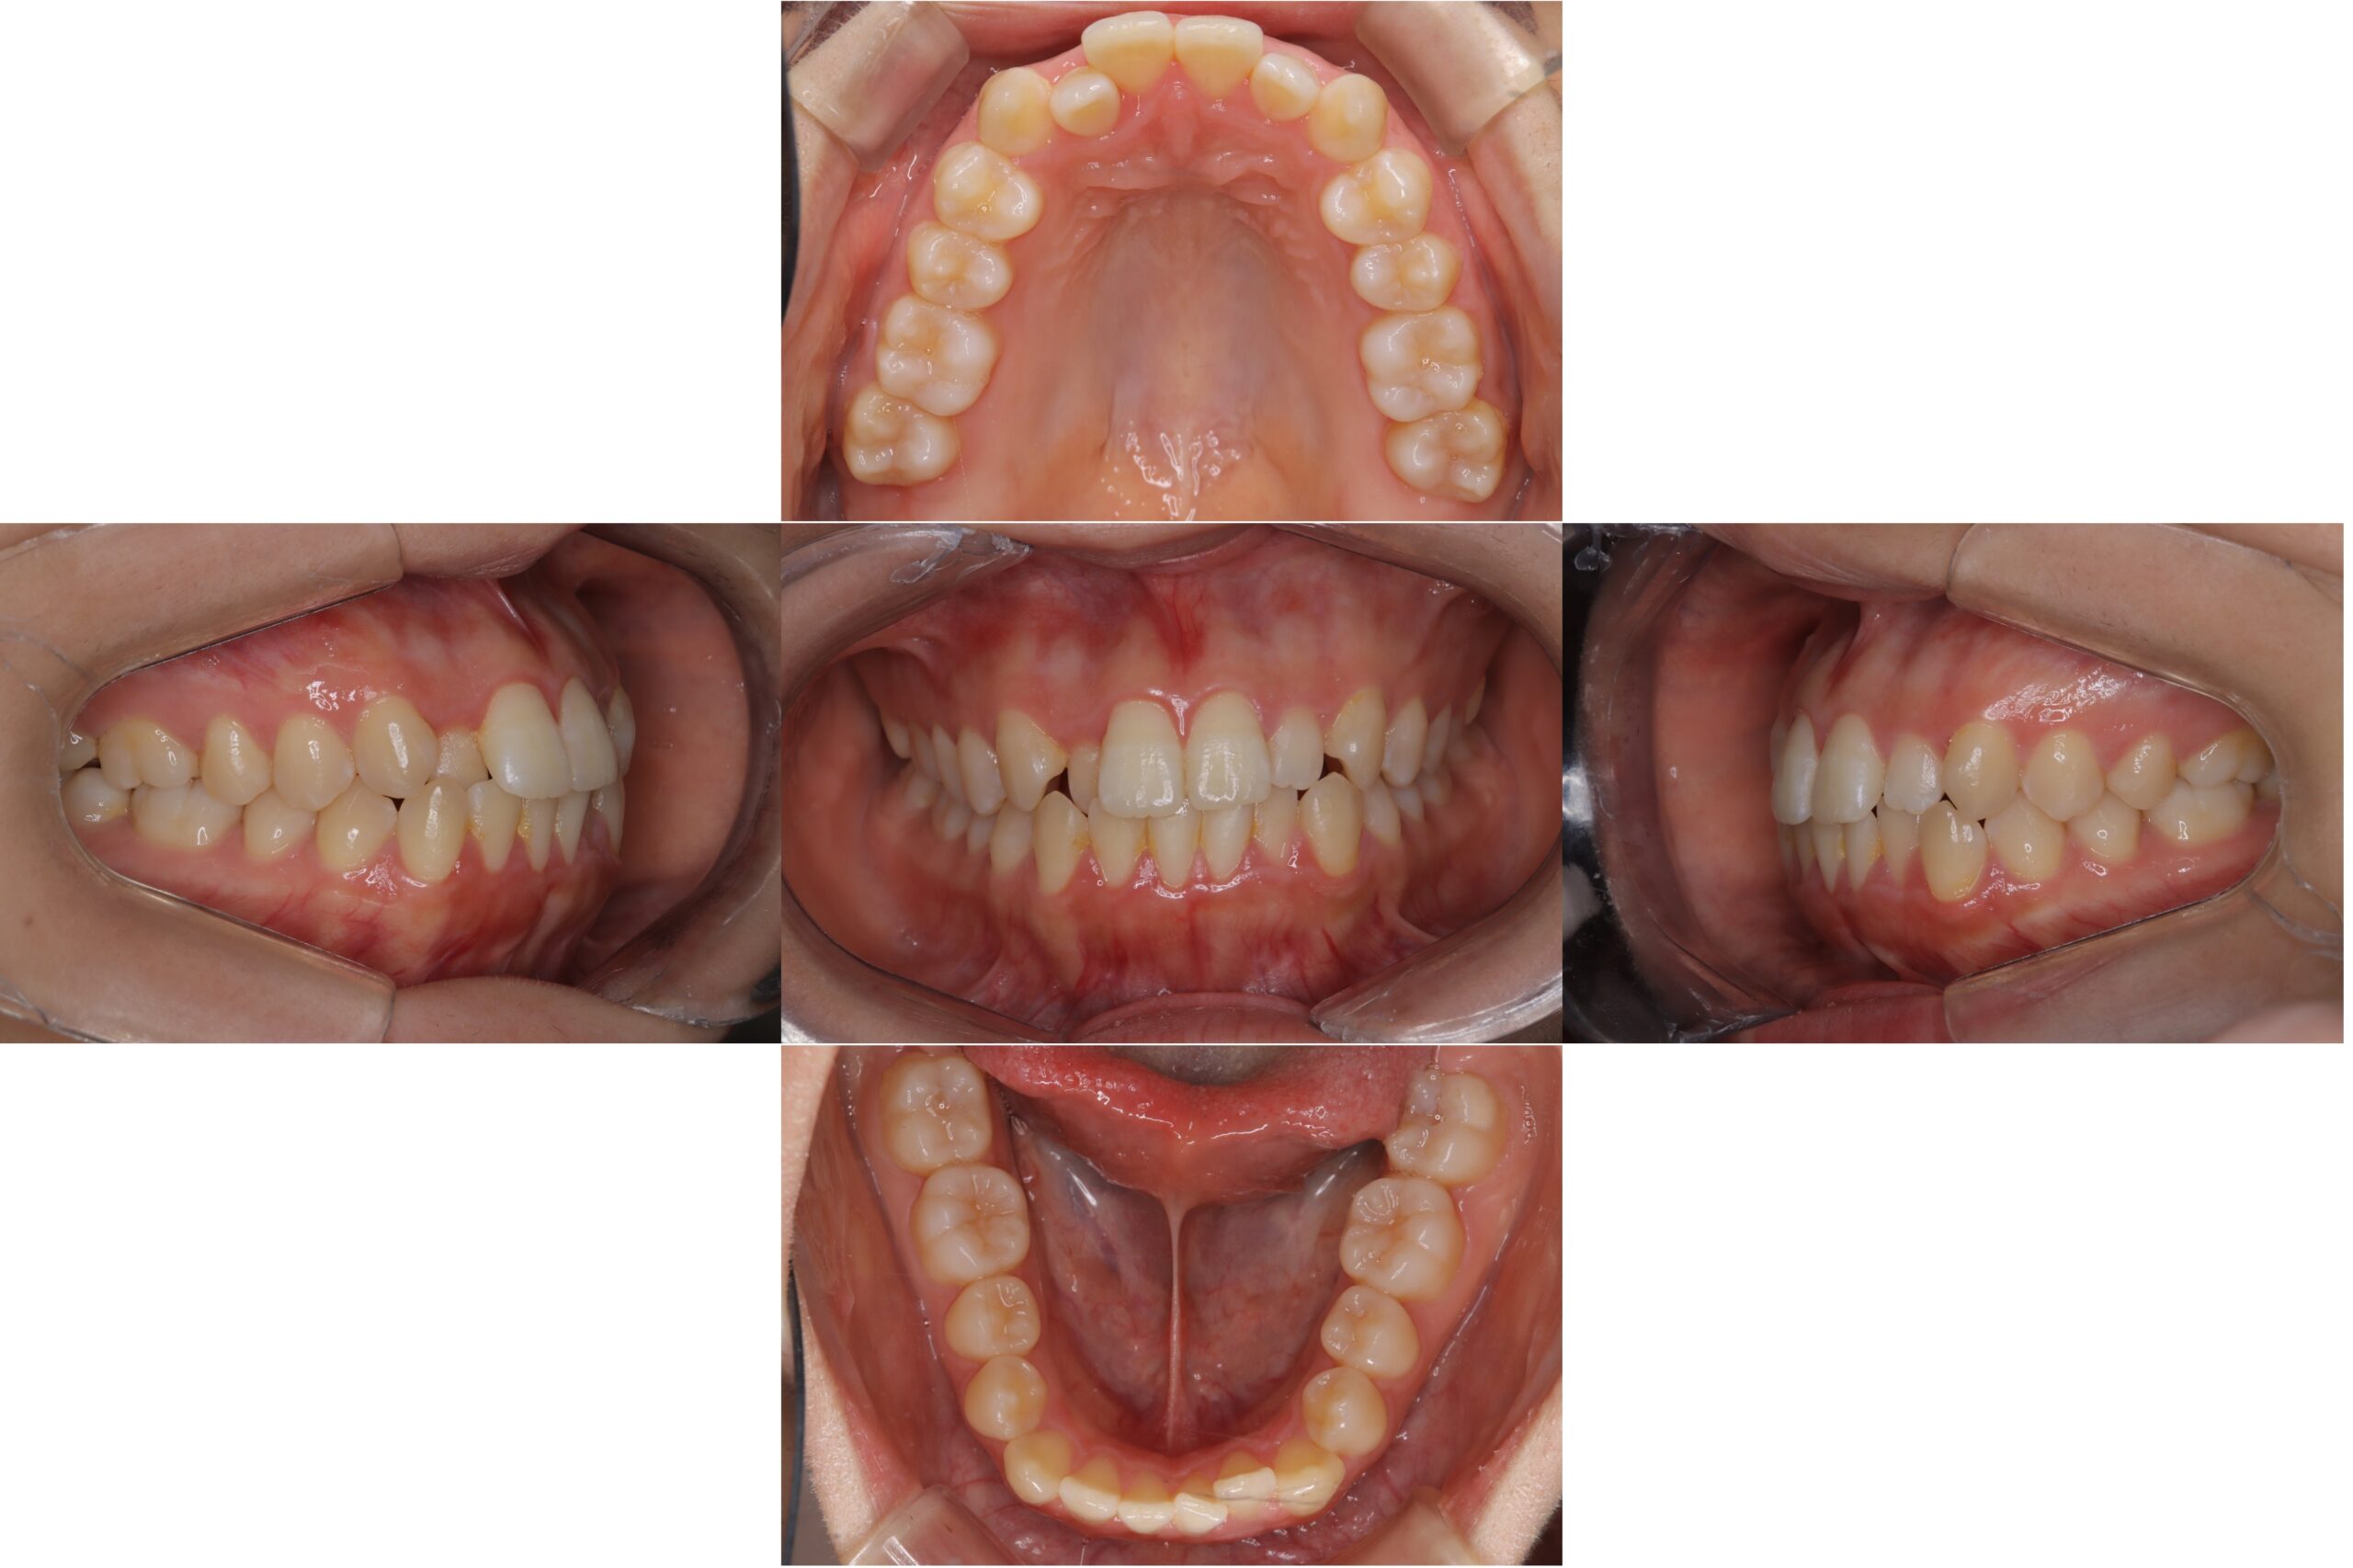

矯正治療

2026-04-22

BEFORE AFTER

翼状捻転:モデレートで矯正

主訴 歯がねじれているのが気になる

期間 1年5カ月

費用 モデレートパッケージ:660,000円(税込み)

治療内容 インビザライン:モデレート

治療に伴うリスク 【マウスピース型矯正装置による治療に関するリスク・副作用】<br /> ・口腔内の状態等により適応とならない場合があります<br /> ・十分な治療効果を得るためには、長時間(目安として1日20時間以上)の装着が必要です<br /> ・装着時間および使用状況により、治療計画通りに進行しない可能性があります<br /> ・治療終了後、保定が不十分な場合には後戻りが生じる可能性があります<br /> ・未承認医療機器を使用する場合があり、医薬品副作用被害救済制度の対象外となることがあります<br /> ・治療結果および治療期間には個人差があります<br /> ・本治療は自由診療(保険適用外)です<br />